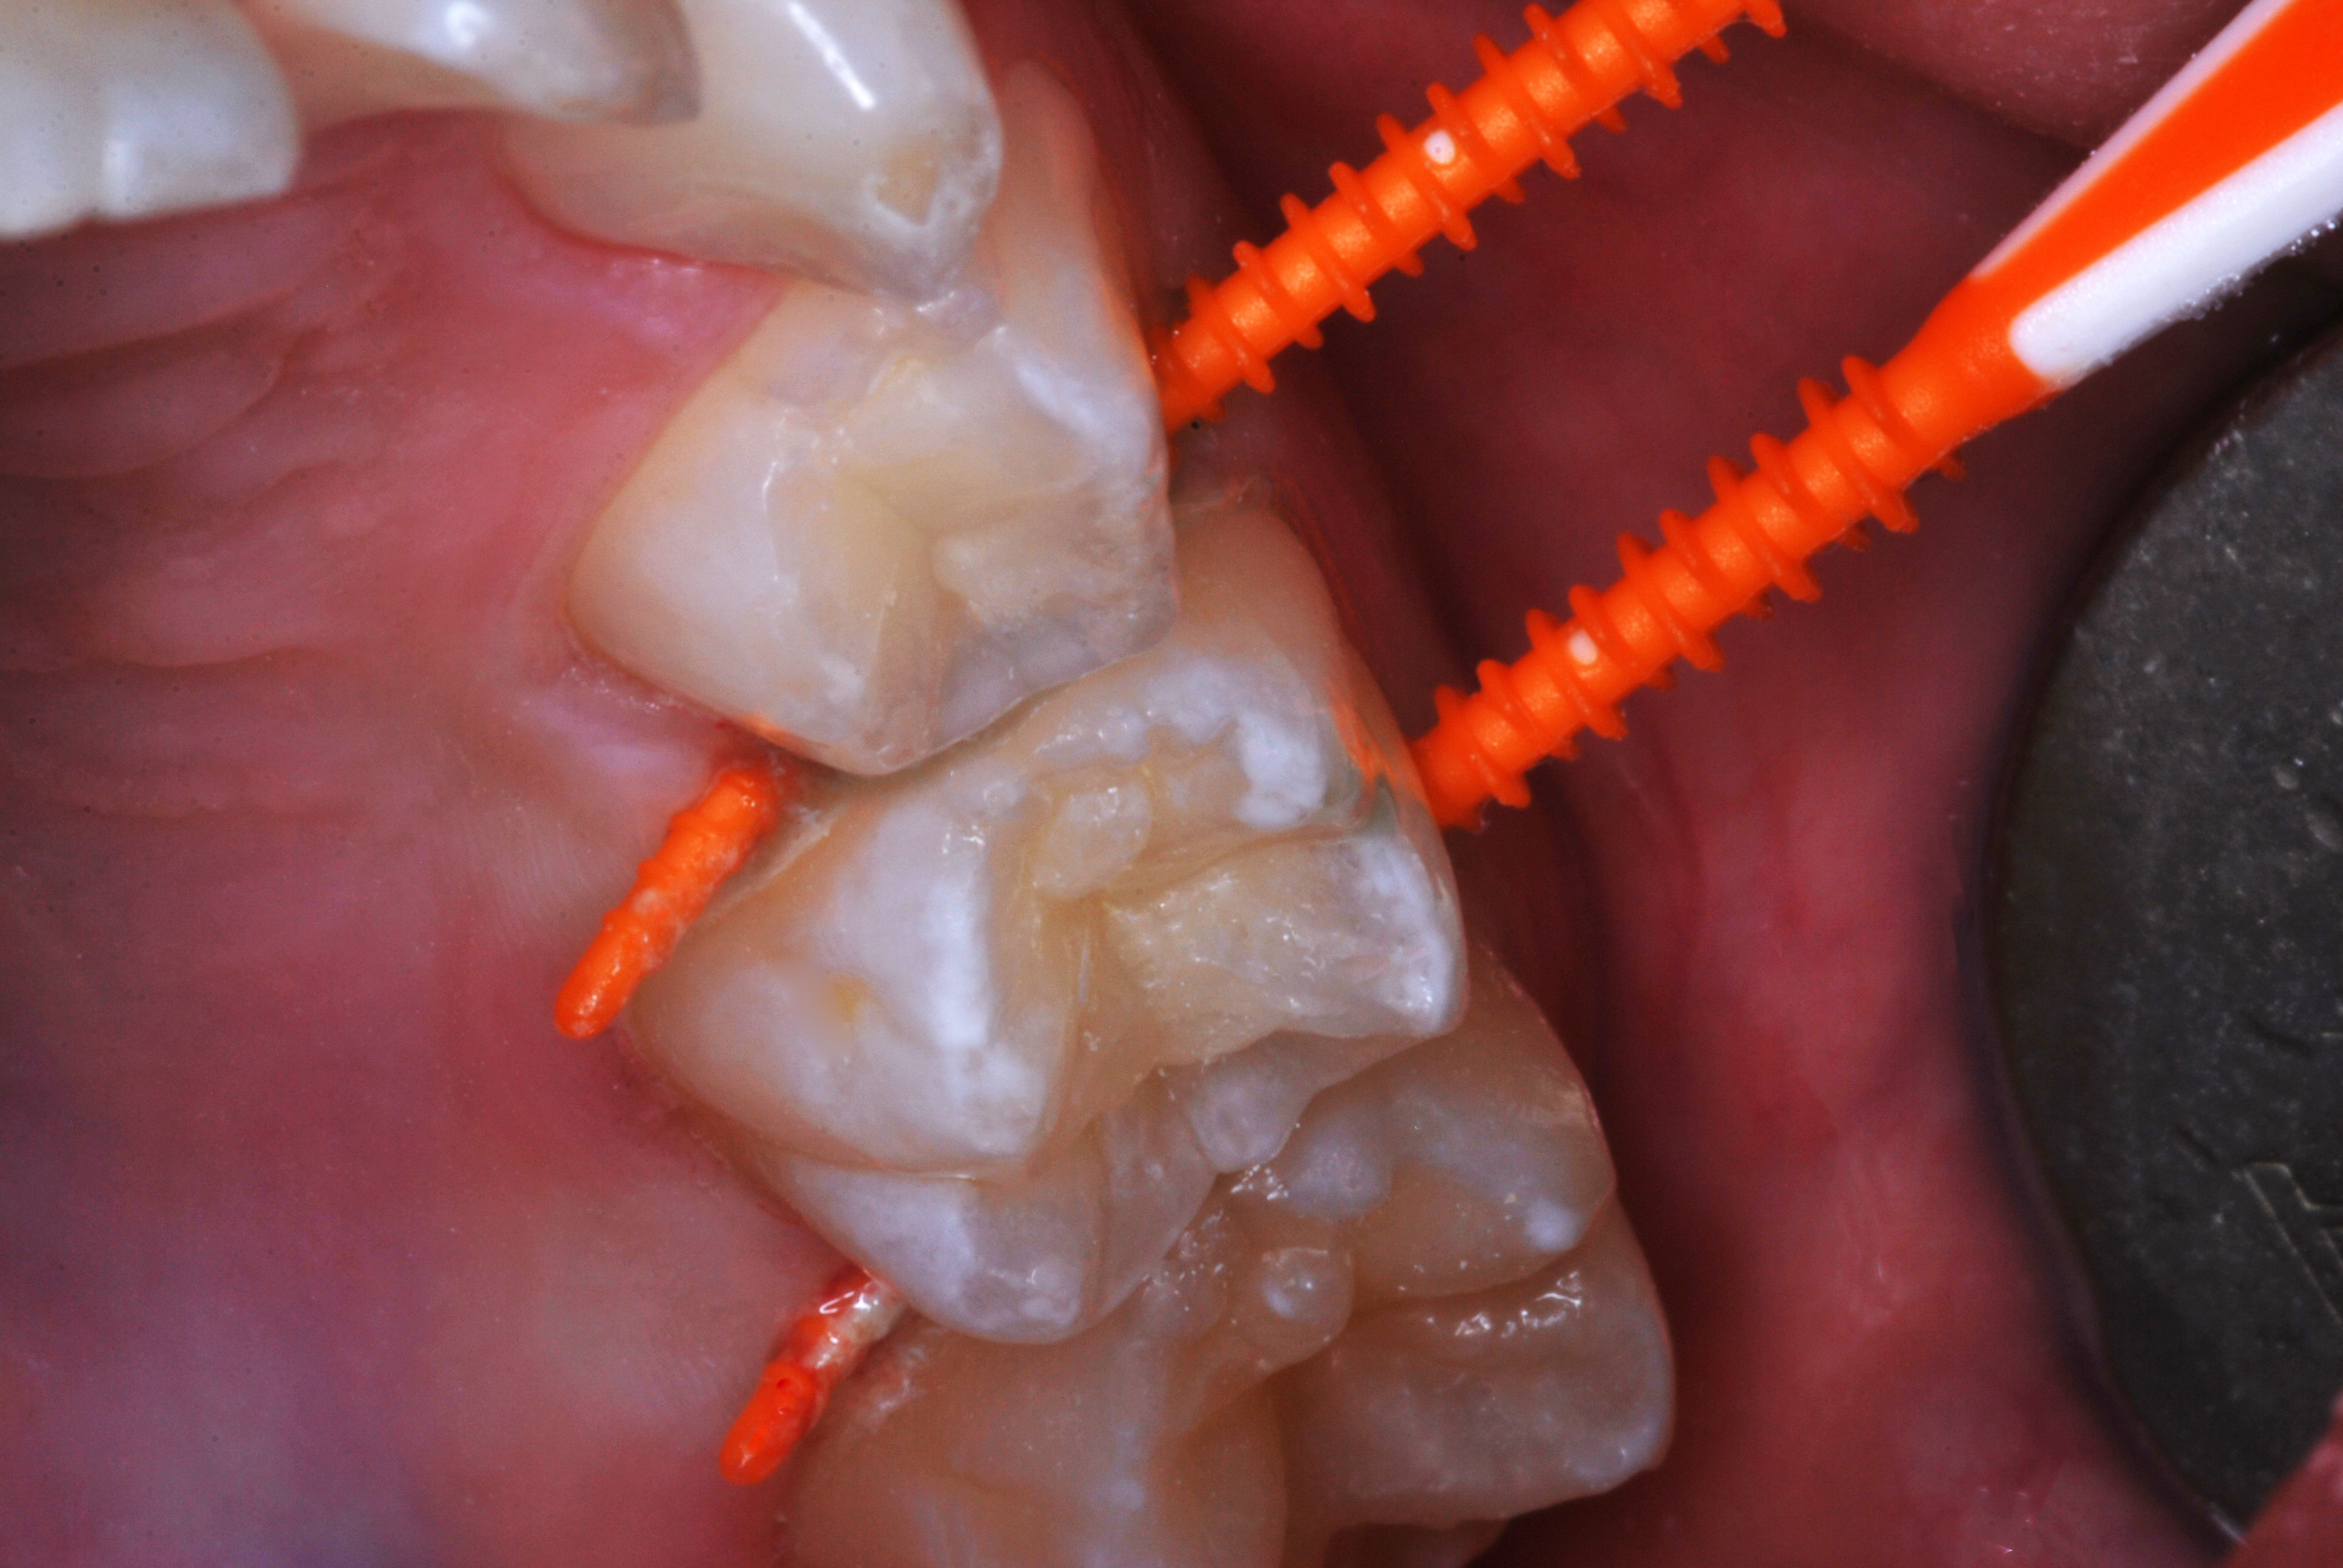

(19.) Example of SDF dental pick application in teenage patient.

Figure 19